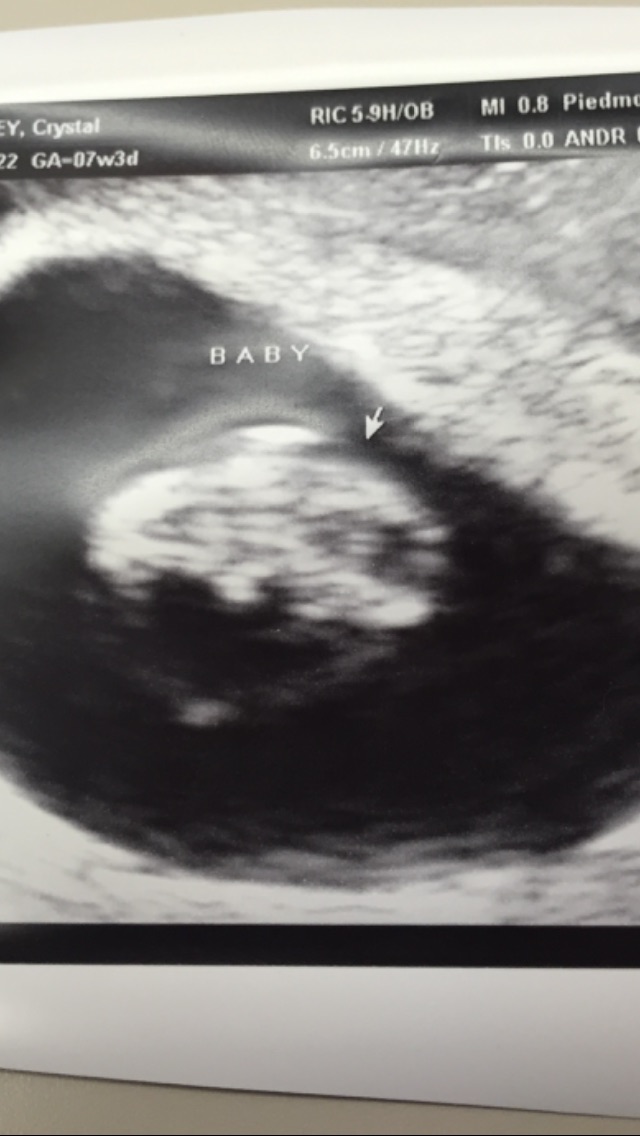

In my personal opinion following the Ramzi Theory it would seem I'm carrying a girl. Ramzi theory is definitely not scientifically proven but I still enjoy doing such things just for fun Anyone else have an opinion on this?

The thick white area to the bottom left seems to be the start of the placenta, so it looks just like the first picture in @adcc43 's example, so boy.